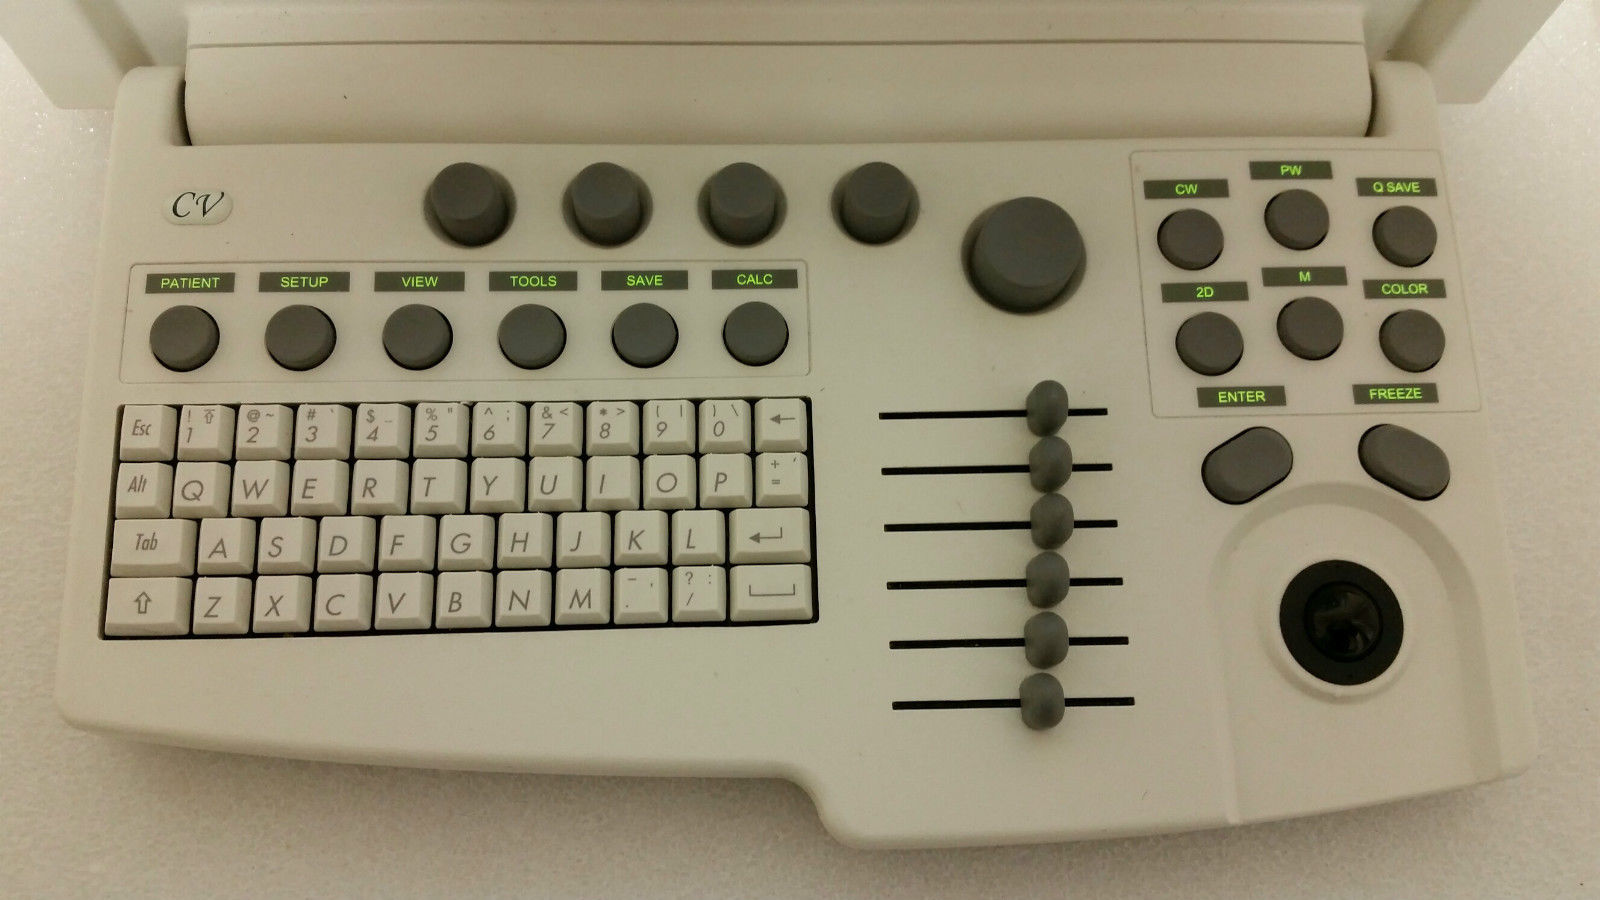

Enhanced User Experience

With a user-friendly interface, the Acuson Cypress simplifies the entire operation process. Health professionals can navigate through its features effortlessly, thanks to the intuitive design and layout. This ease of use not only speeds up the workflow but also improves the overall user satisfaction. Therefore, healthcare practitioners spend less time on technicalities and more on patient care and diagnostics.